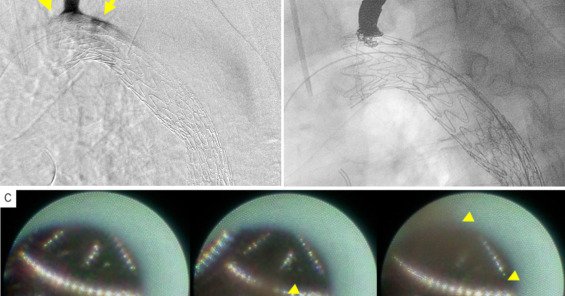

π©Έπ§ Cracking chronic venous occlusions sharply. Using the TipsStar Steerable Cannula, 5 patients with total venous occlusions were successfully recanalized. Precision steering = safer, faster, sharper access. π https://t.co/6iSRRujBXo

Chronic total venous occlusions are challenging to recanalize due to anatomic complexity and limited directional control. This report describes the use of the TipsStar Steerable Cannula (BD; Franklin...